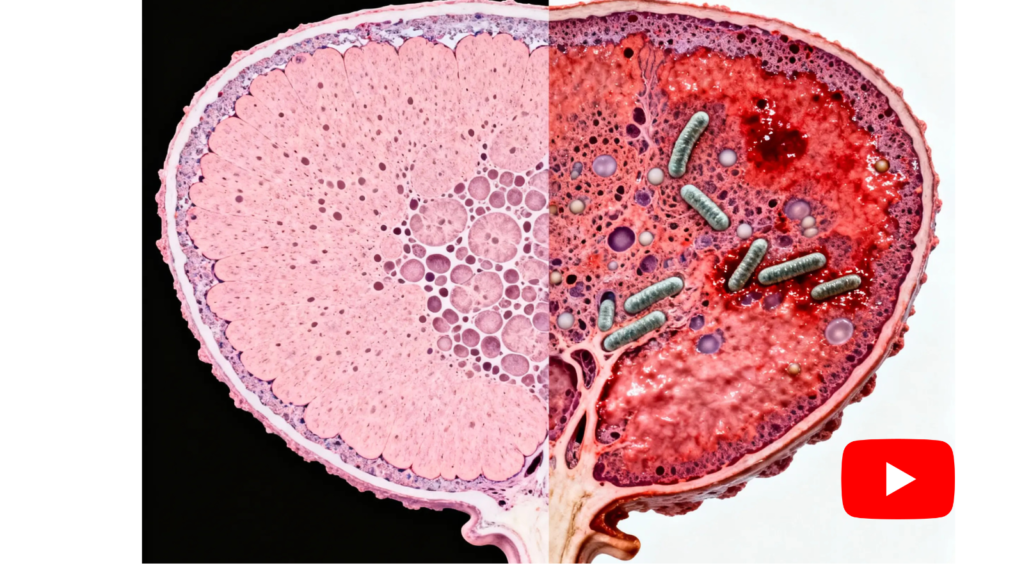

Recent clinical research from top urologists has uncovered something shocking: the root cause of prostate swelling isn't just hormones or age — it's a bacterial imbalance.

When harmful bacteria colonize prostate tissue, they trigger a self-perpetuating cycle of inflammation. Your body sends immune cells to fight the bacteria, but those same cells cause swelling, block urinary flow, and create pressure. Over time, this cycle worsens — unless you break it at the source._

The 4 Stages of Prostate Inflammation

Which stage are you in? Each level makes recovery harder…

Stage 1

Mild Discomfort

Subtle signs that usually appear at night. Inflammation begins to press against the urethra.

Damage Level: 25%

Stage 2

Daily Distraction

Urgency and burning start to interfere with sleep and routine. Internal swelling continues to advance.

Damage Level: 50%

Stage 3

Life Disruption

Inflammation dominates daily life — you start planning everything around the nearest bathroom.

Damage Level: 75%

Stage 4

Functional Collapse

Advanced inflammation: risk of infection, urinary retention, and loss of quality of life.

Damage Level: 100%